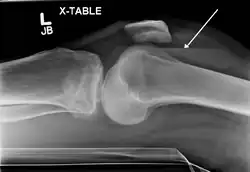

Lipohemarthrosis due to a tibial plateau fracture -

Subtle tibial plateau fracture on an AP X ray of the knee -

A tibial plateau fracture seen on X-ray